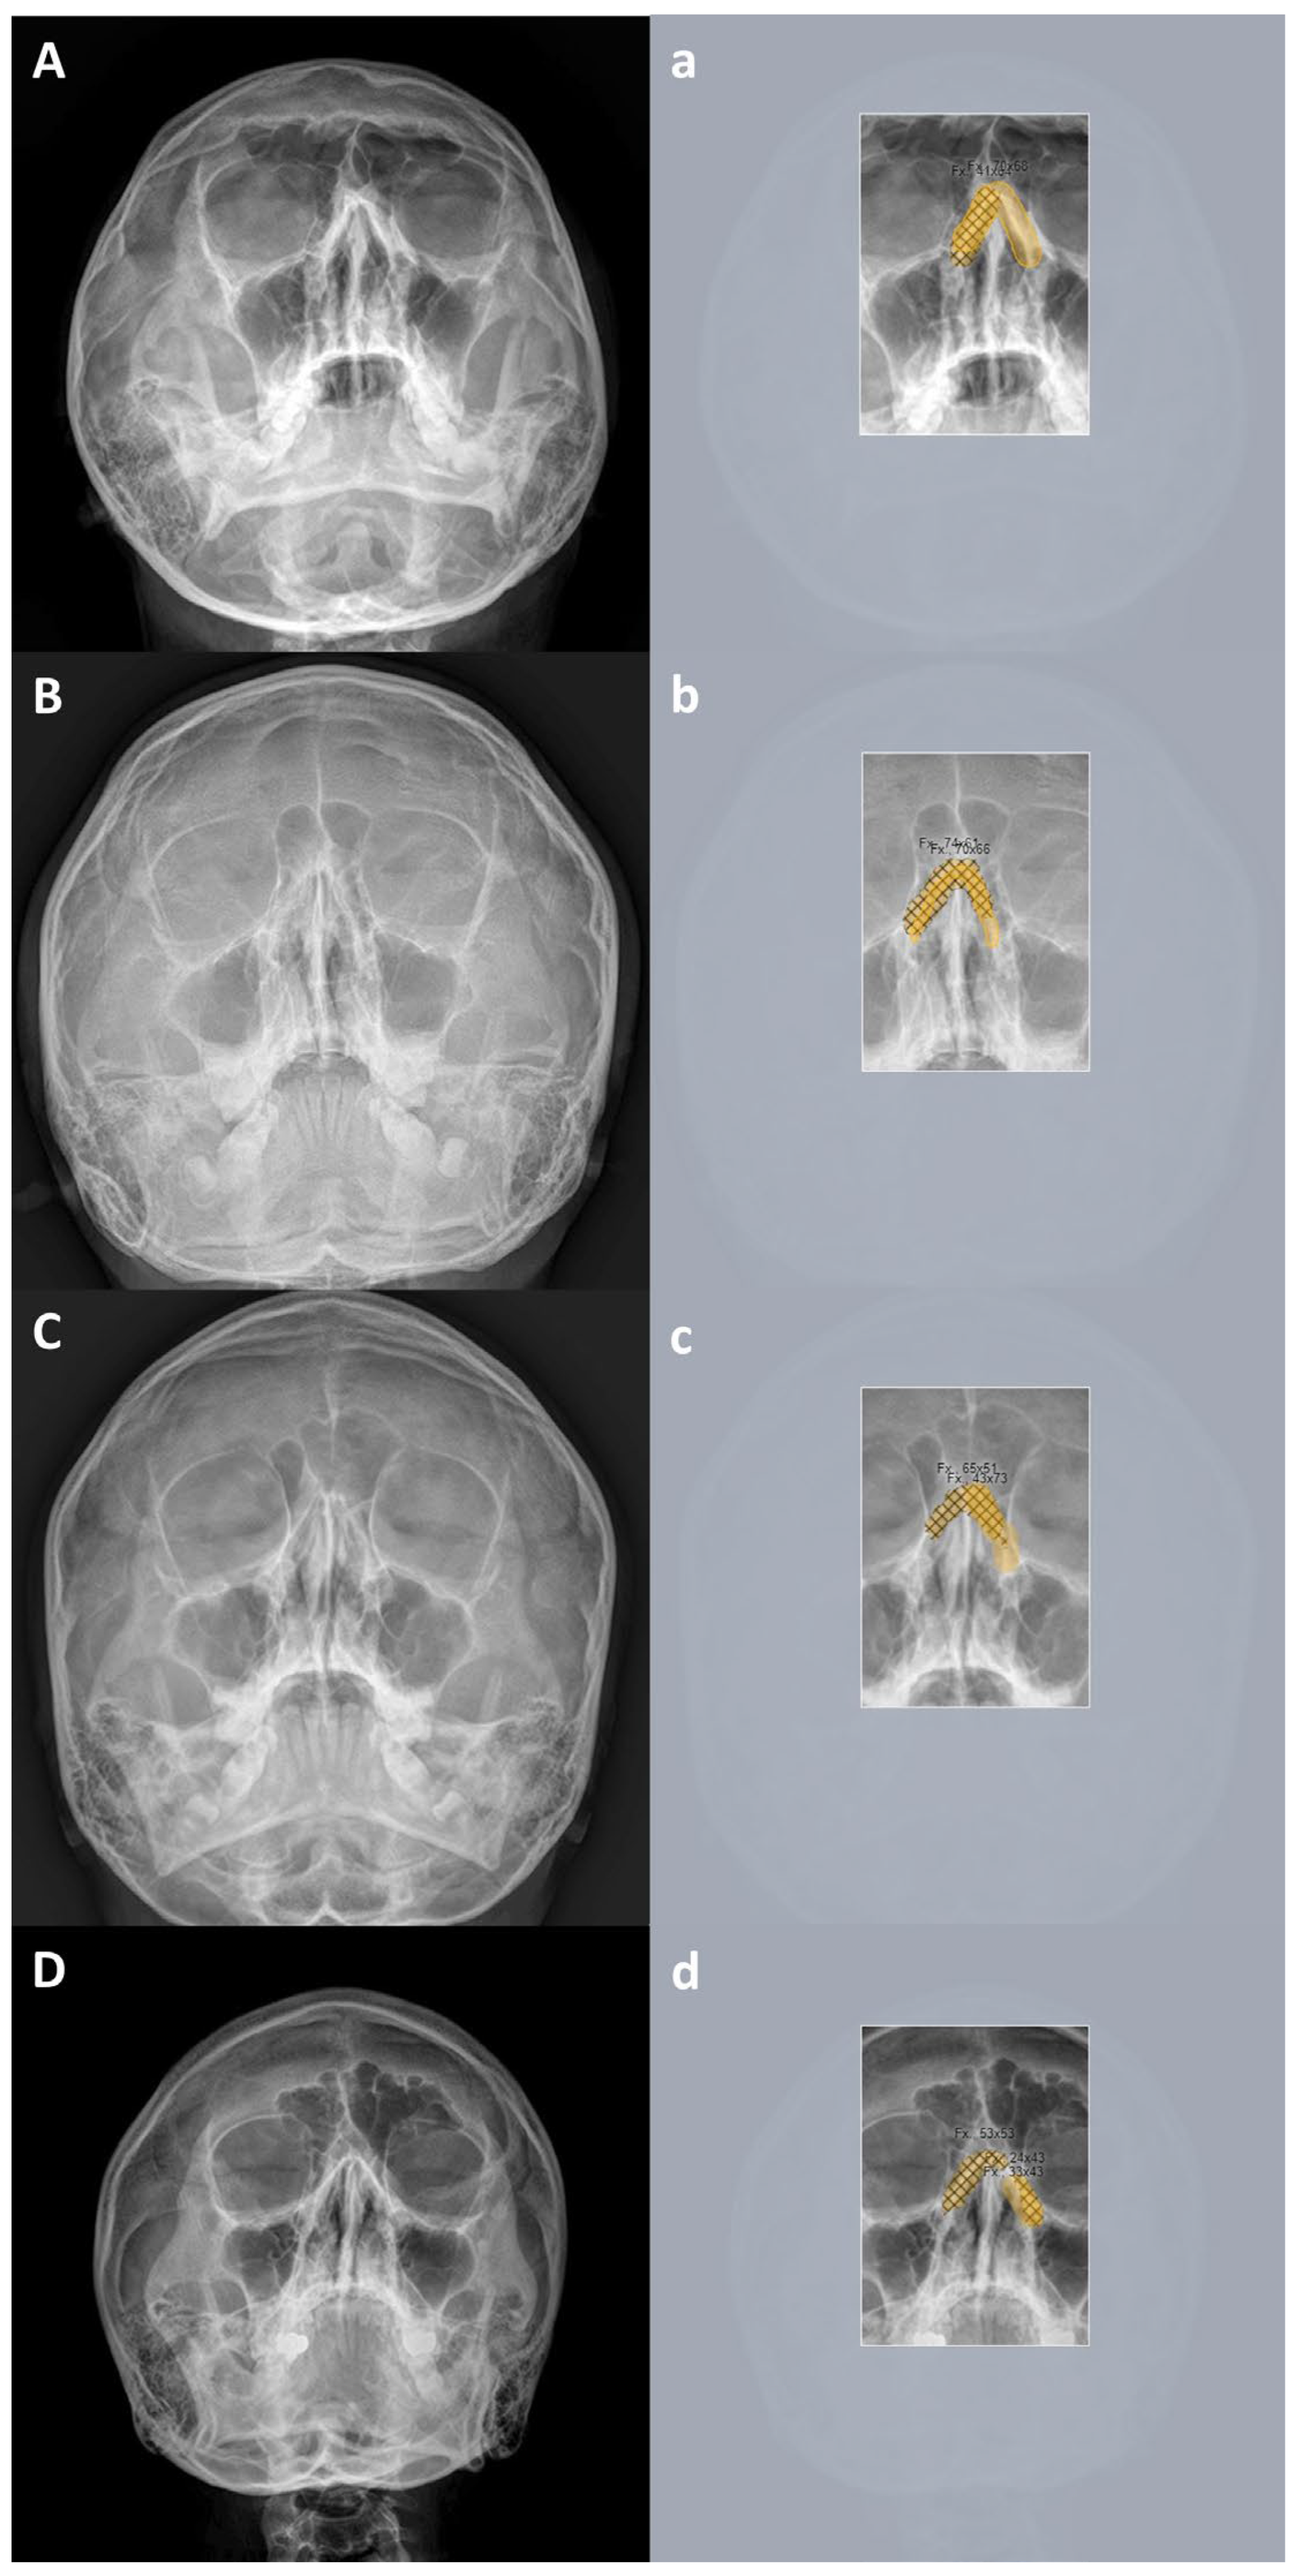

3.3. True Positive and False Positive of Deep Learning Models